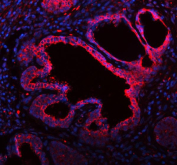

Immunofluorescent staining of FFPE human prostate cancer tissue with ME3 antibody (red) and DAPI nuclear stain (blue). HIER: steam section in pH8 EDTA buffer for 20 min.